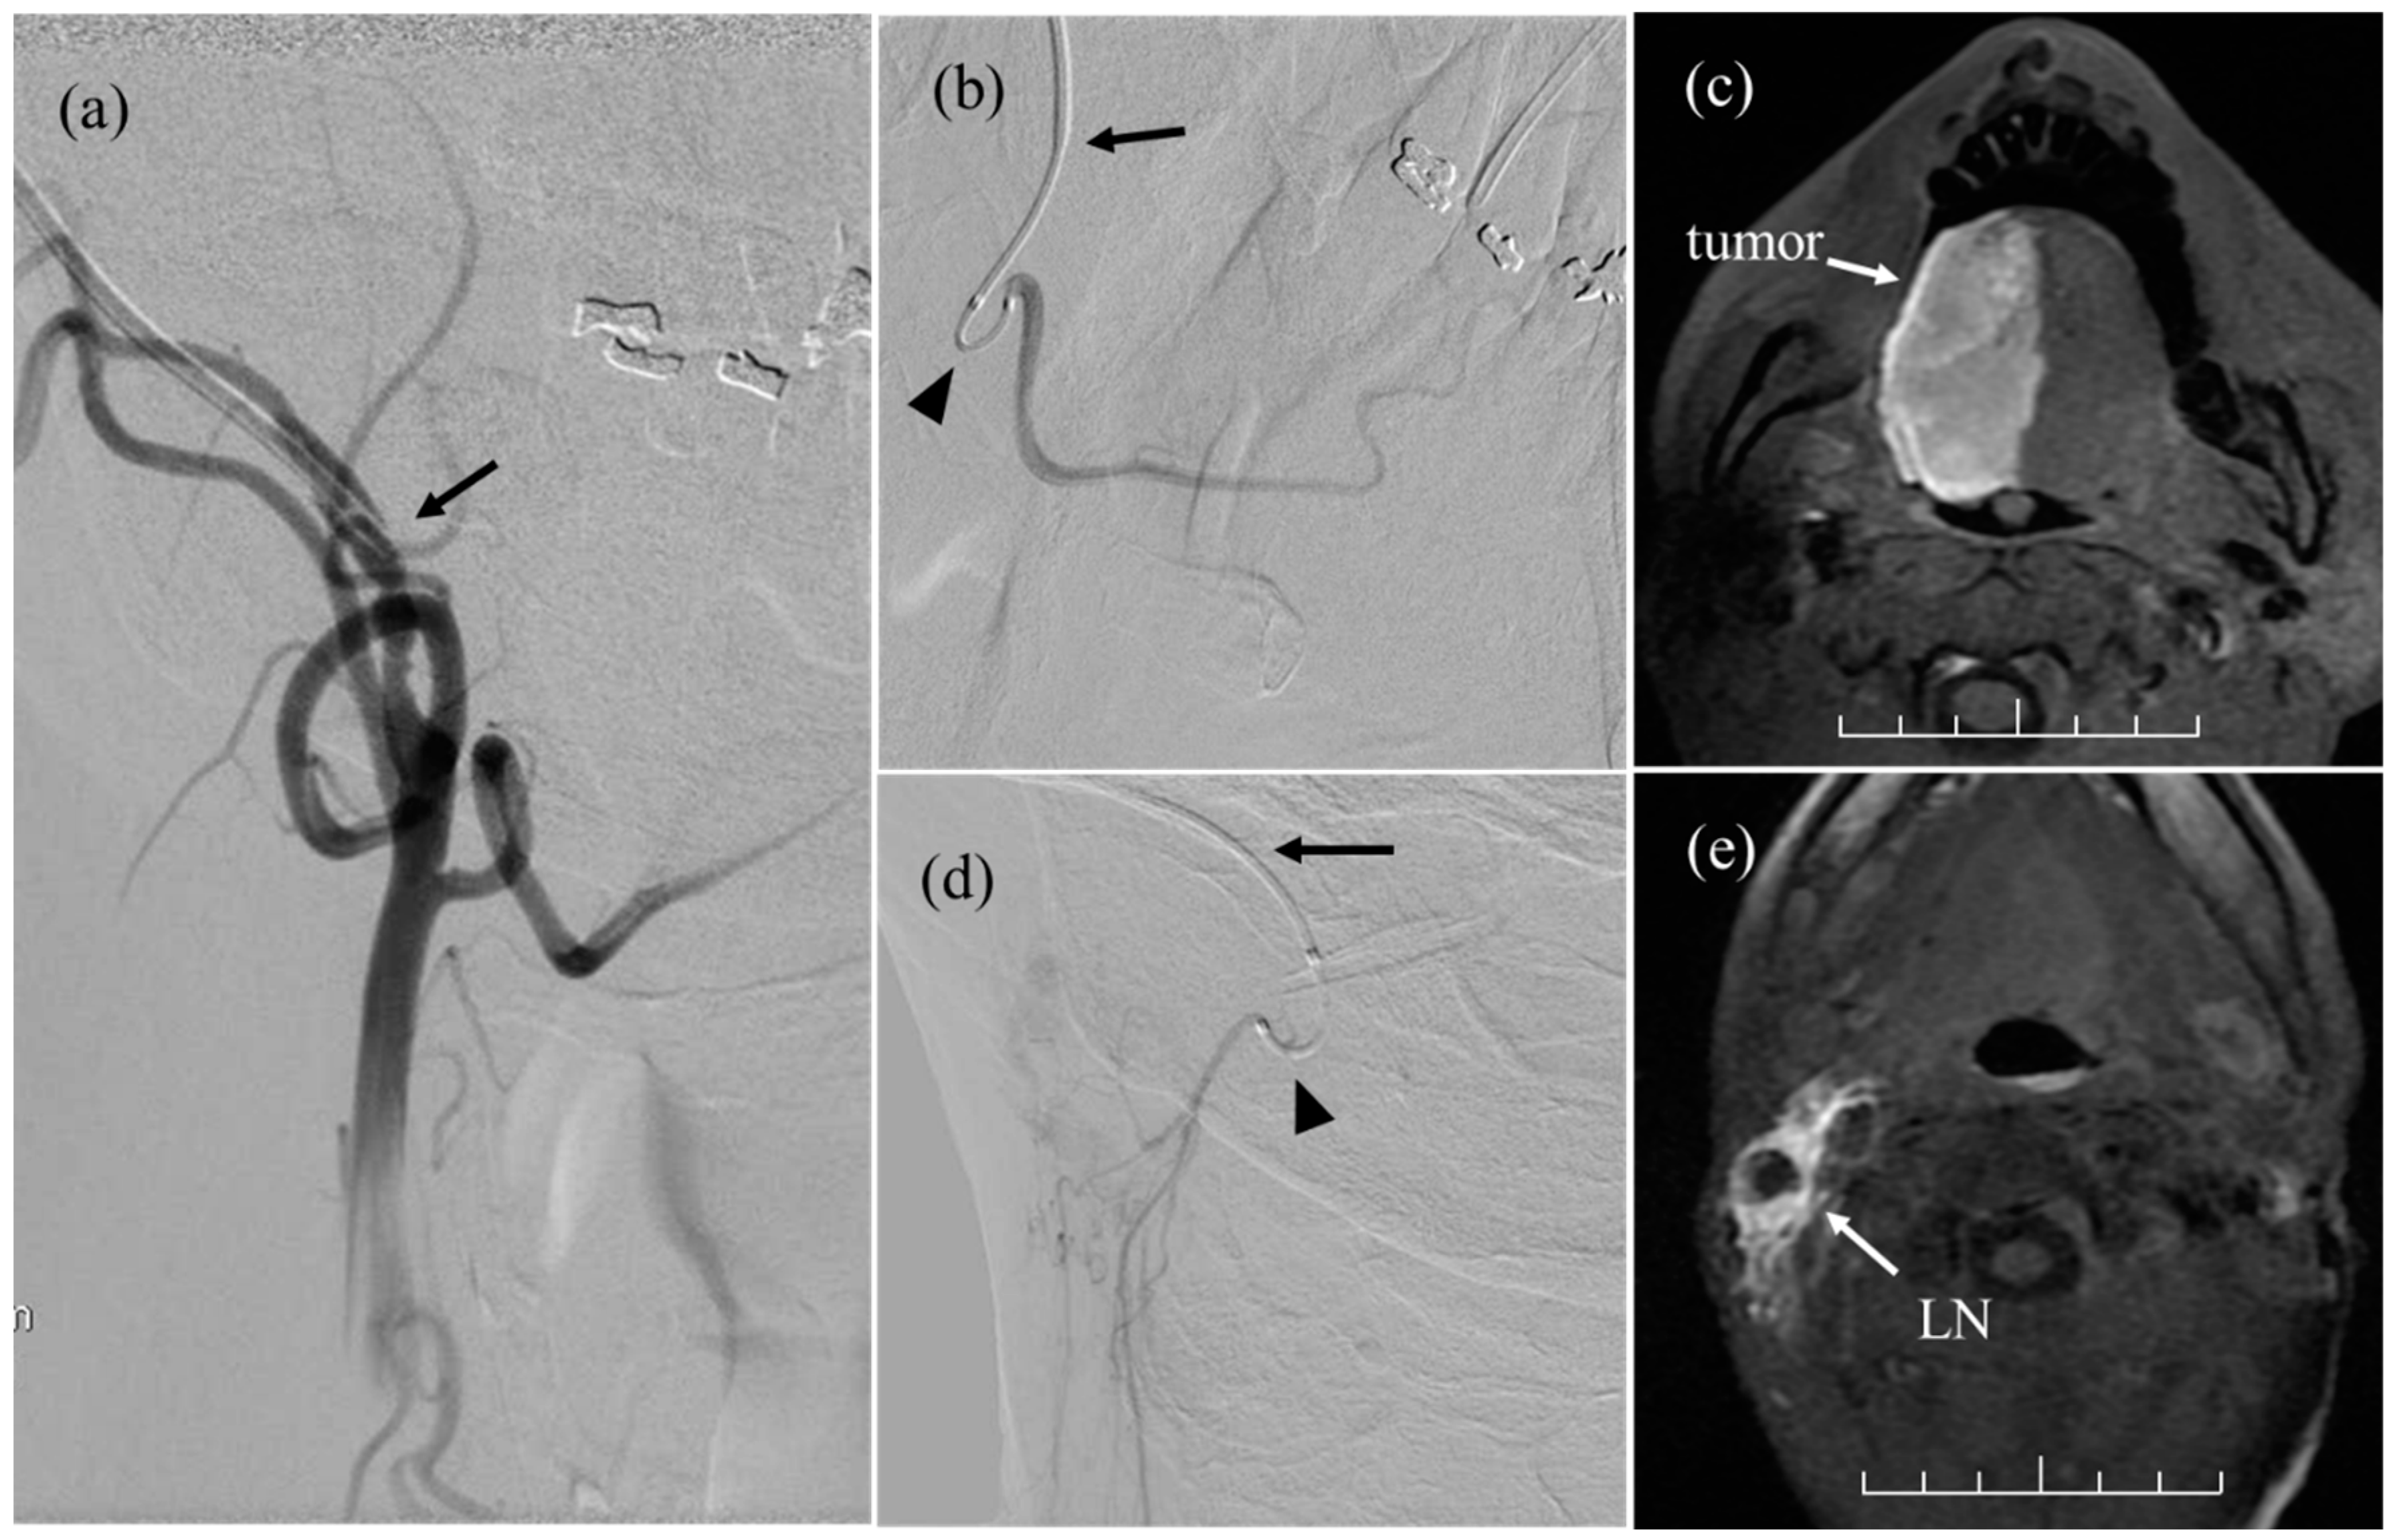

Superselective angiography of the left external carotid artery images Beading In Carotid Artery Arterial imaging with ct angiography, mr angiography and digital subtraction angiography (dsa) may be used to. Fibromuscular dysplasia (fmd) is a nonatherosclerotic disease of medium‐sized vessels that can present with arterial stenosis, beading, dissection, and. Patients with carotid artery fmd may experience headaches (especially migraine type), neck pain, and a pulsatile ringing or swooshing sound in the ears. Fibromuscular dysplasia. Beading In Carotid Artery.

Cancers Free FullText Initial Experience of IntraArterial Beading In Carotid Artery Patients with carotid artery fmd may experience headaches (especially migraine type), neck pain, and a pulsatile ringing or swooshing sound in the ears. If you have fmd in a specific artery that supplies blood to your brain (called the carotid artery) you may feel headaches, neck. Arterial imaging with ct angiography, mr angiography and digital subtraction angiography (dsa) may be. Beading In Carotid Artery.